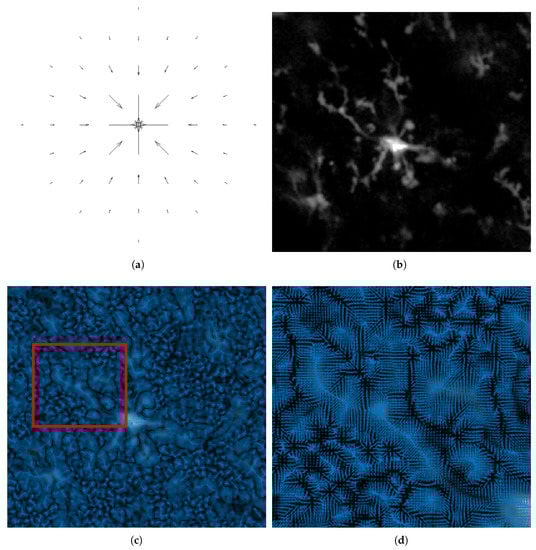

2. Background on Vector Field Convolution

3.3. C3VFC: Tracing Glia in 3D Temporal Images

3.6. Concentric Circles, VFC, Critical Point Detection

3.7. Tracing Cells Back to Soma